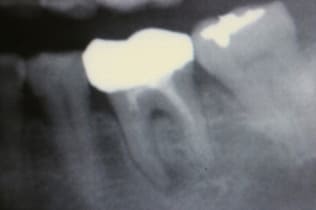

根管治療は無菌の根管を作り、緊密な根管充填が絶対条件です。歯の寿命がこれで決まると言っても過言ではありません。下の写真は根管充填不良により引き起こされた、根尖性歯周炎の状態です。左が根管治療前、右が根管充填後のレントゲン写真。

-

術前

CWCT法による根管治療の術後